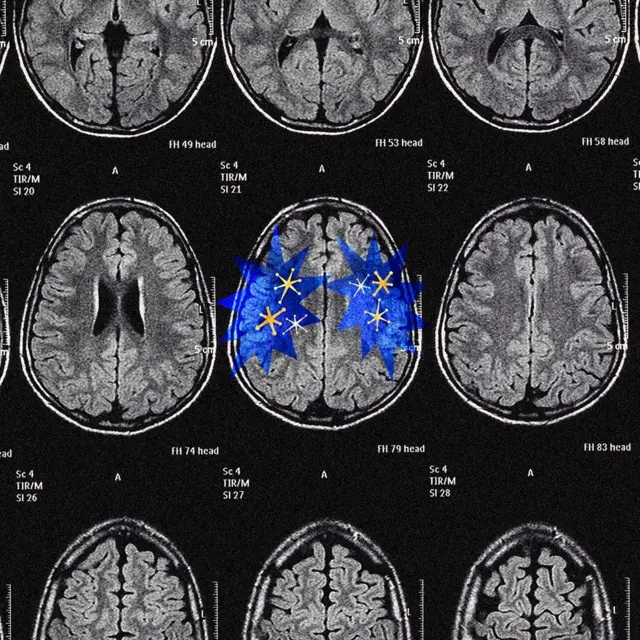

हे समजून घेण्यासाठी आपल्याला मेंदूच्या दोन भागांकडे पाहावं लागेल - मेंदूचा बाह्य भाग (सेरेब्रल कॉर्टेक्स) आणि बक्षीस प्रणाली म्हणजेच रिवॉर्ड सिस्टिम (ज्यामध्ये डोपामाइनही येतं), जे आपल्याला वेगवेगळ्या दिशांकडे नेतात.

सेरेब्रल कॉर्टेक्स म्हणजे आपला मेंदू समजून घेण्याची यंत्रणा. तो आपल्यासाठी जगाचं एक मॉडेल तयार करतो आणि मग त्याला बाह्य जगाशी जुळवण्याचा प्रयत्न करतो किंवा बाह्य जगाला आपल्या कल्पनेशी जुळवतो. त्याला नेमकी खरी माहिती नको असते, तर फक्त आपल्याला हवा असणाऱ्या गोष्टींसोबत वास्तव जुळवणं महत्त्वाचं असतं, तेही कोणत्याही परिस्थितीत.

आणि खरंच, मेंदूत असा दुसरा भाग आहे ज्याचं काम फक्त हे ढकलणं म्हणजे पुश करणं आहे. याला बक्षीस प्रणाली (रिवॉर्ड सिस्टिम) म्हणतात, आणि डोपामाइन हे त्याचं मुख्य साधन आहे, जे आपले निर्णय आणि प्रेरणा मार्गदर्शन करण्यासाठी वापरतं. डोपामाइन हेच आपल्याला पुढे ढकलत राहतं, कधी चांगल्या तर कधी भयानक पद्धतीने.

काही रुग्ण कधी कधी एक-दोन शब्द बोलायचे; काही जण जर त्यांच्याकडे चेंडू फेकला तर पकडायचे; अन्न तोंडात ठेवलं तर चावायचे, पण स्वतःहून कधीच अन्न घेऊन खाण्याचा प्रयत्न करत नव्हते. आज आपल्याला समजतं की, हा रोग मेंदूत सबस्टँशिया निग्रा नावाच्या भागाला प्रभावित करायचा, म्हणजे मेंदूतला एक असा भाग जो डोपामाइन तयार करतो.

एल-डोपा हे औषध सॅक्सने रोझ आरला काही काळ दैनंदिन जीवनात परत आणण्यासाठी वापरले, ते डोपामाइन तयार होण्यापूर्वीचं रसायन आहे. सॅक्सला तेव्हा याचा नेमका प्रभाव समजला नाही, पण नंतरच्या संशोधनानुसार आपण अंदाज लावू शकतो की रोझ आरच्या मेंदूमध्ये काय घडत होतं. तिच्या सबस्टँशिया निग्रा नावाच्या डोपामाइन तयार करणाऱ्या भागातील बहुतांश पेशी मृत होत्या, पण काही न्यूरॉन्स अजूनही जिवंत होते.